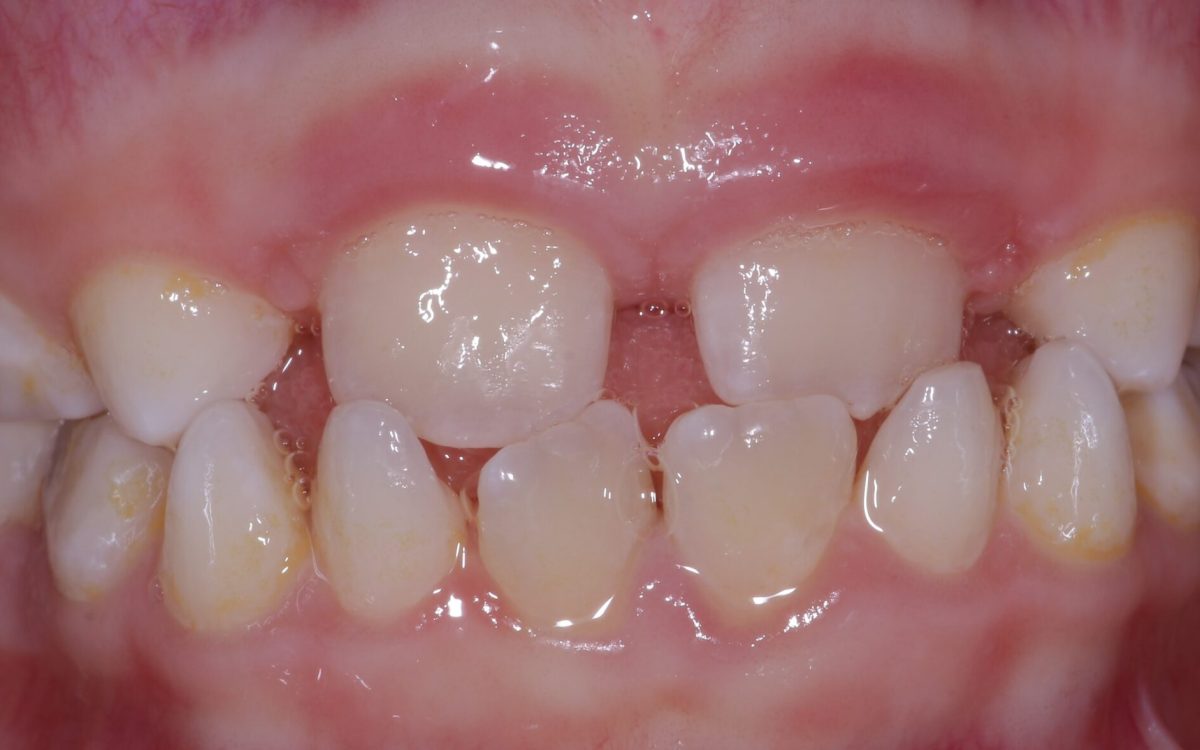

Gyermekeink fogai eredendően egészségesek, helyes fejlődésük, a helyes szájápolás korai elsajátítása, majd maradó fogaik egészségének megőrzése olyan feladat, amit jobb minél hamarabb megtanulni.

Javasoljuk, hogy 2-3 éves korban kezdjük meg a fogászathoz szoktatást . Ebben a korban még nincs fogászati probléma, de ilyenkor van rá lehetőség, hogy ismerkedjenek az új helyszínnel, barátkozzanak az asszisztenssel és a fogorvossal. Ha majd később szükséges kezelés, már egy megszokott környezetben, számára ismert emberekkel találkozik, és a meglévő bizalom segít neki majd a kezelésben.

Noha a tejfogak ideiglenesek, mégis fontos feladatot látnak el. A rágás, erőteljes harapás, az állcsont és az arcizmok, sőt a beszéd, kiejtés helyes fejlődésében vesznek részt.

A tejfog betegségeire legegyszerűbb módszer a prevenció! Amennyiben mégis megtörténik a baj, több lehetőségünk van a probléma megszüntetésére:

A szuvas rész eltávolítása után fogszínű, esztétikus, fehér tömőanyaggal fedjük be a „lyukat”, így óvjuk a fogat, és segítünk abban, hogy ellássa a feladatát.

A tejfog is rendelkezik gyökérrel, belsejükben ugyanúgy idegszálak futnak, amelyek a fog életben tartásáért felelnek. Abban az esetben, amikor a gyulladás olyan mértékű, hogy a szuvasságot okozó baktériumok a fog belsejébe jutottak, gyökérkezelésre van szükség. A maradó fogakhoz képest azonban kicsit eltérő ez a kezelés, hiszen a tejfogak gyökerei a fogváltáskor felszívódnak.